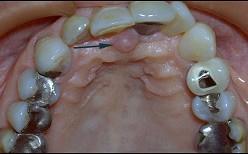

问题 切牙乳突是排列上中切牙的解剖标志、是因为()

选项 A.切牙乳突的位置变化较小 B.切牙乳突位于上颌腭中缝的前端 C.切牙乳突下方为切牙孔、排牙时要防止此处压迫 D.切牙乳突与上颌中切牙之间有较稳定的关系 E.两个上中切牙的交界线应以切牙乳实为准

答案 D